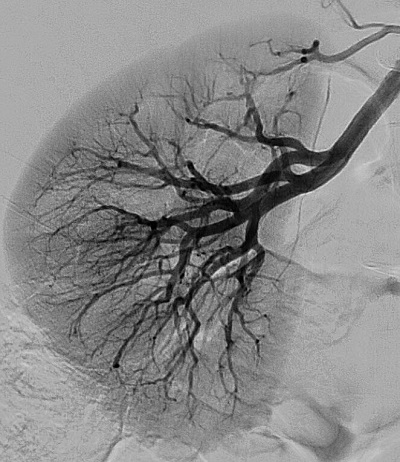

Interventional X-ray

Philips’ AlluraClarity is a revolutionary new generation of interventional X-ray systems providing high quality imaging for a full range of clinical procedures at ultra low dose levels. The AlluraClarity platform offers high-quality imaging at ultra low dose levels, enhanced work environment for staff through active management of scatter radiation, and expands treatment options-enables longer procedures to treat obese and high-risk patients with confidence.

High-quality at ultra low dose levels